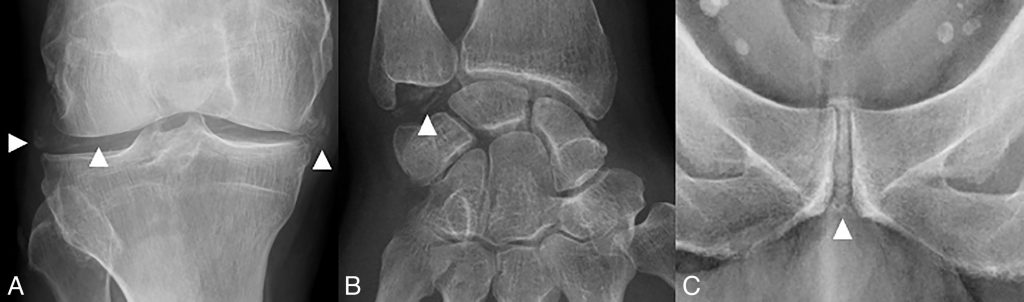

Calcifications cartilagineuses le plus souvent linéaires (figure 75.1).

- Atteinte fréquente des fibrocartilages (ménisque, ligament triangulaire du poignet, symphyse pubienne).

Fig. 75.1 Chondrocalcinose.

Radiographies du genou de face montrant des calcifications caractéristiques des ménisques et du cartilage (têtes de flèche) (A), du poignet de face montrant des calcifications du ligament triangulaire (tête de flèche) (B), et du fibrocartilage de la symphyse pubienne (tête de flèche) (C).

Source : CERF, CNEBMN, 2022.